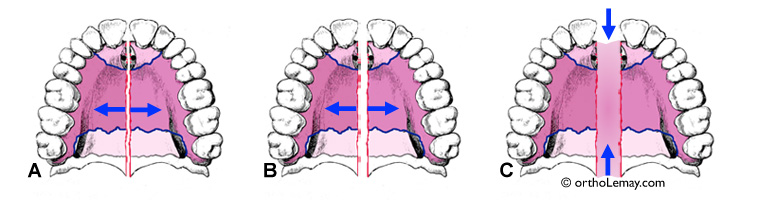

Pendant l’expansion maxillaire, l’ouverture de la suture se fait progressivement mais rapidement :

(A) Les 3-4 premiers tours d’activation de l’appareil ne produiront pas de changements visibles, mais commencent tout de même à agir sur la suture.

(B) Après quelques tours, la suture commence à s’ouvrir. Un diastème (espace) qui apparaît entre les incisives centrales supérieures confirme que l’ouverture se produit normalement au niveau de la suture. L’activation est continuée jusqu’à ce que la quantité d’expansion désirée soit obtenue (± 3 semaines).

(C) À la fin de la période d’activation, la suture est maintenue ouverte en gardant l’appareil en bouche approximativement 3 mois sans faire de tours de vis. Cette période d’immobilisation est nécessaire afin de permettre une reminéralisation de la zone d’ouverture de la suture. Après cette période, l’appareil d’expansion peut être enlevé. L’espace entre les incisives centrales commence à se refermer pendant l’immobilisation.

L’ouverture de la suture n’est pas visible en bouche, mais l’est sur une radiographie. Les radiographies ci-dessous montrent un palais avec un appareil d’expansion en place pendant l’ouverture de la suture palatine durant la phase d’expansion maxillaire rapide. Lorsque la suture ouvre normalement, un diastème (espace) apparaîtra entre les incisives centrales supérieures.